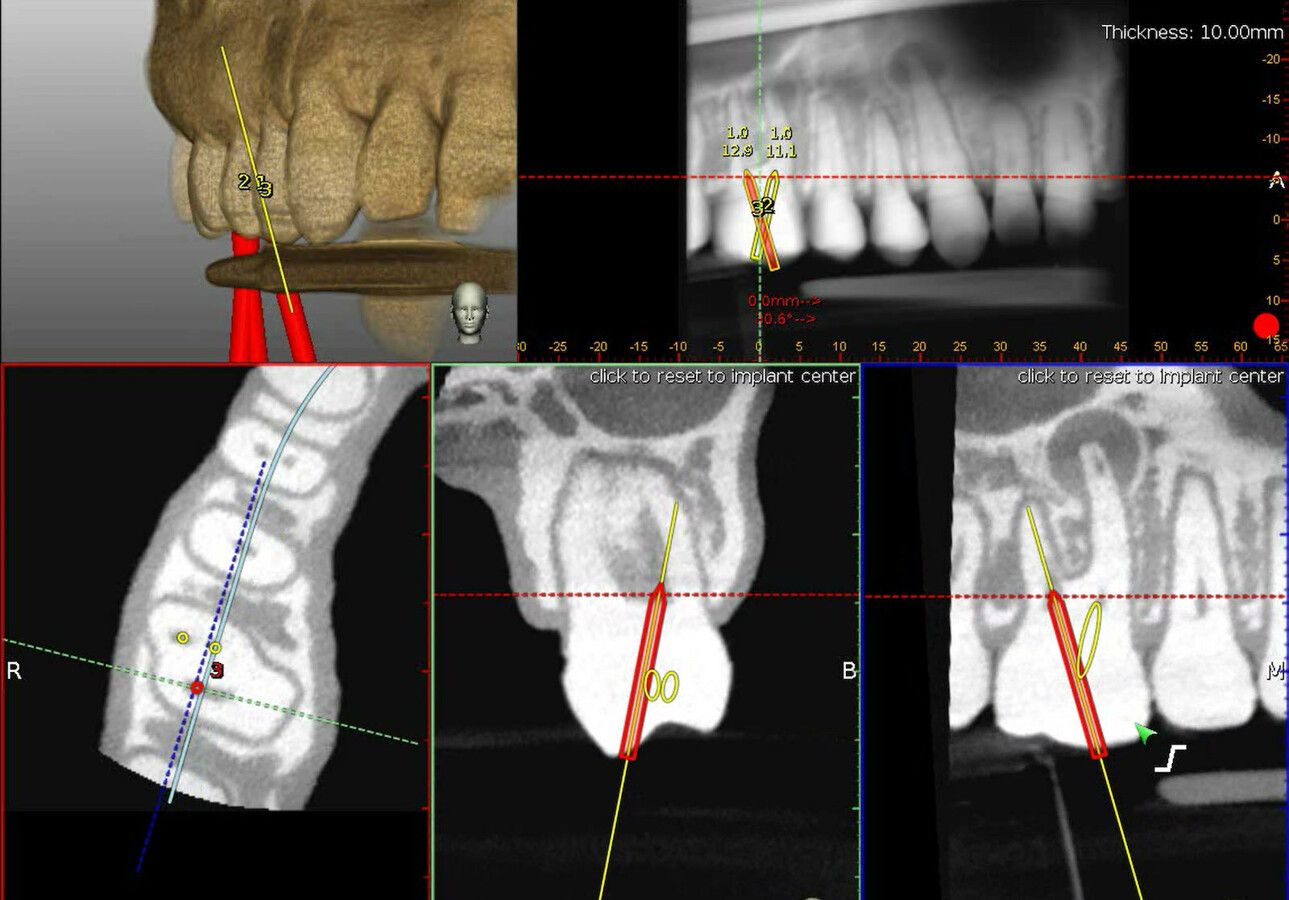

The scheme of the dental implant navigation system (DINS) is based on Dynamic Navigation System In Endodontics in the present case report, a dynamic navigation implant system was used for guided endodontics. This scoping review (scr) was conducted to map the existing literature on dynamic. learn how dynamic navigation (dn) can guide endodontic procedures such as root canal localization and trephination based. inherited from implant dentistry, the dynamic navigation system (dns) is a breakthrough. Dynamic Navigation System In Endodontics.